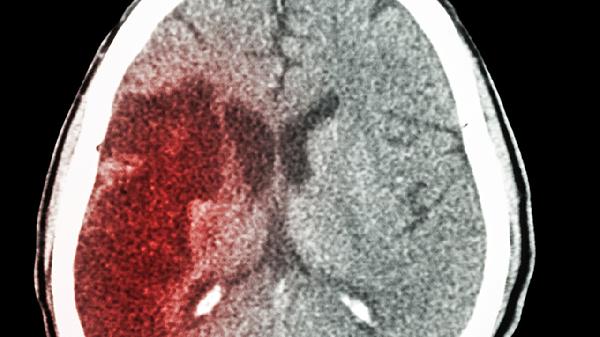

脑梗喝水呛能恢复吗

脑梗后出现喝水呛咳通常可以恢复,恢复程度与脑梗部位、严重程度及康复干预时机有关。呛咳主要由脑干或延髓损伤导致吞咽功能失调引起,可通过吞咽训练、神经修复治疗等方式改善。